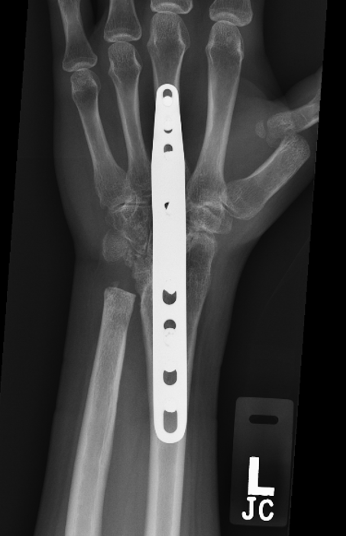

Fusion operations: Fusion is the term given whereby the joint is removed and the bones either side are pinned and held together, so that the bones heal as one piece. The wrist can be partially or fully fused. These operations sacrifice movement of the wrist for pain relief. This is usually the most reliable and predictable treatment for intractable wrist arthritis with up to 85% satisfaction.